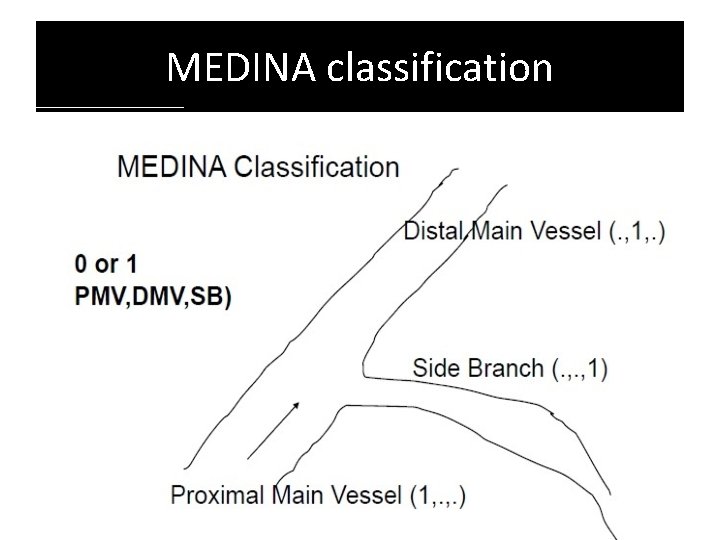

MEDINA classification

Limitations Does not take intoaccount 1. 2. 3. 4. 5. 6. Length of disease in the ostium of the SB Length of the LMCA before the bifurcation Trifurcation Vessel angulation No differentiation is madebetween a normal segment (lesion free segment) and a < 5 0 % lesion presenceof calcifications is not identified